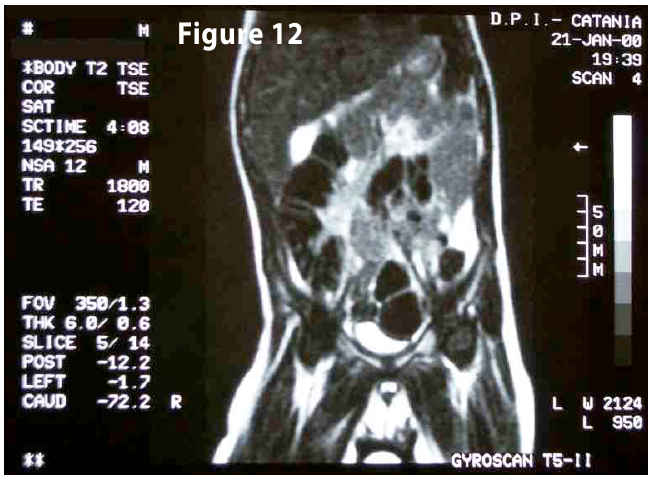

Figure12